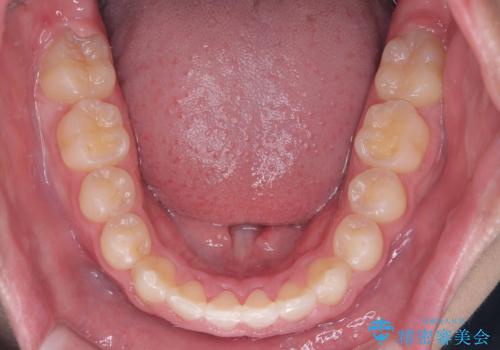

八重歯・歯並びのデコボコとディープバイトを改善した抜歯ワイヤー矯正症例

矯正の精密検査の結果上顎左右4番の計2本を抜歯し、審美性に配慮したワイヤー矯正装置(審美装置)を用いて治療を行いました。

八重歯などの歯列のデコボコが綺麗に改善され、患者様にも大変喜んでいただけました。また、咬み合わせが深い「ディープバイト」も併せて改善し、見た目だけでなく機能面でもバランスの取れた咬合を獲得しています。